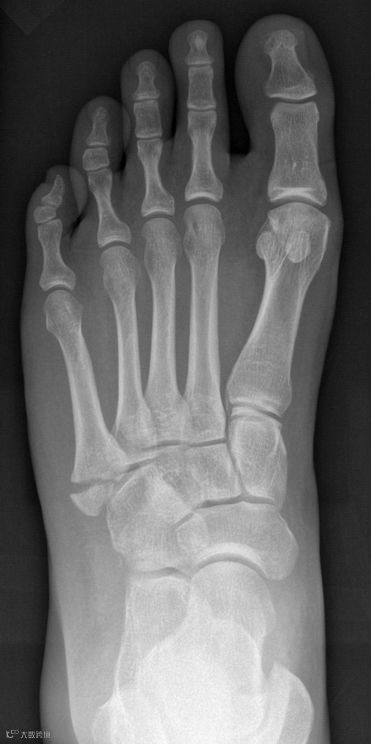

X线图像:

X线检查是怀疑骨骼肌肉损伤的首选方式;

此例假性琼斯撕脱骨折的发生是由于跖屈时腓骨短肌肌腱牵拉,常发生踩在马路的边缘或者楼梯边缘时。在网球、篮球运动员中也常出现,有人称之为网球骨折;

鉴别假性琼斯骨折/琼斯骨折也很关键,因为两者治疗方式不同。